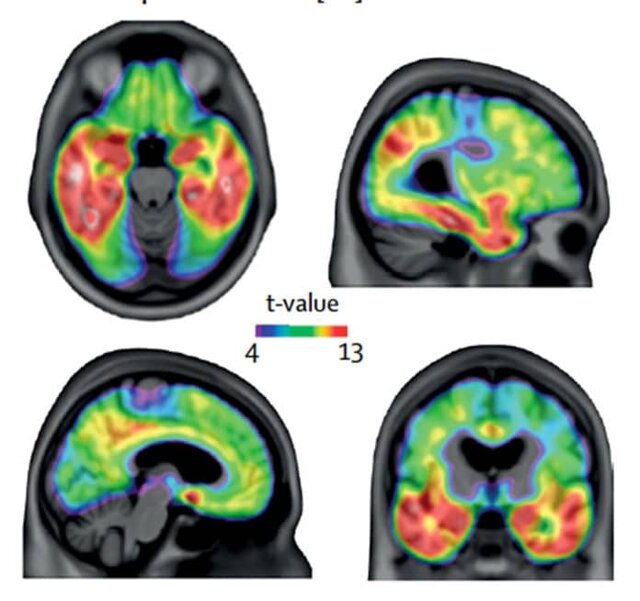

دکتر "ثاریک پاسکوال" (Tharick Pascoal) متخصص اعصاب دانشگاه مک گیل گفت: این یک چالش بود زیرا این پروتئین‌ها به مقدار بسیار کمی در خون هستند. ما انتظار نداشتیم که نتایج یک آزمایش خون ساده بتواند بسیار مشابه نتایج آزمایش‌هایی مانند "پت" (PET ) یا مایع مغزی نخاعی باشد.